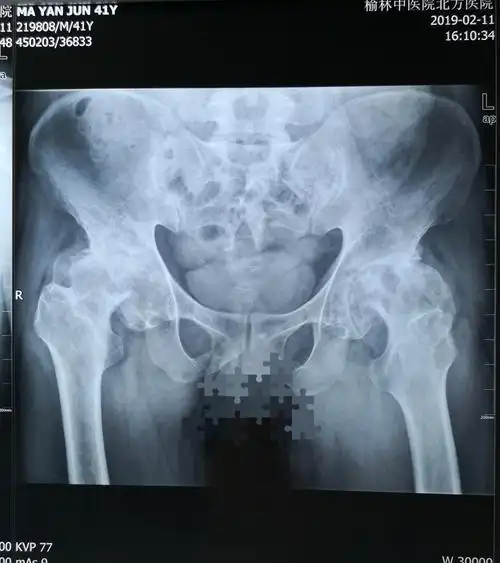

术前髋关节正位x线片